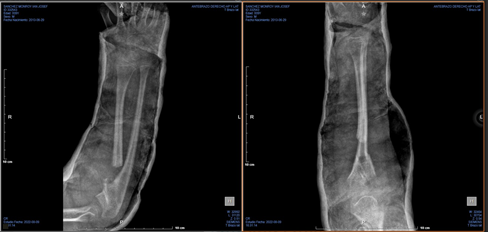

A 5 cm incision was made over the proximal forearm. Careful dissection was performed to identify and protect the posterior interosseous nerve. An osteotomy of the radial diaphysis was conducted, followed by diaphysectomy with smoothing of the bone edges. Bone wax was applied to the osteotomy site to prevent new bone formation. Intraoperative assessment confirmed an increased range of pronation-supination. A brachio-palmar cast was used in a neutral position for six weeks (Figure 2).

Figure 2 Immediate postoperative anteroposterior and lateral radiographs of the right forearm

Caption: Radiographs demonstrating the right forearm immediately after osteotomy and resection of the synostosis.

During clinical and radiographic follow-up, the patient demonstrated significant range of motion improvement, with supination increasing to +20° and pronation maintained at +70°. The Failla scale score improved to 12 points, indicating good function. Follow-up radiographs showed no recurrence of synostosis at 12 months (Figure 3). The patient is undergoing rehabilitation therapy to maintain and enhance his range of motion.

Figure 3 Anteroposterior and lateral radiographs of the right forearm 12 months post-surgery.

Caption: Radiographs showing maintained separation of the radius and ulna without recurrence of synostosis one year after surgery.